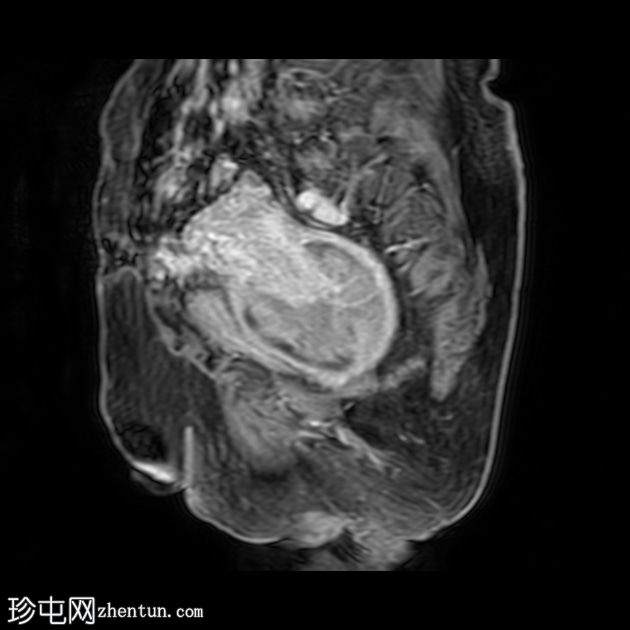

矢状位

T2

子宫呈U形,宫底轮廓消失,宫底突出至扩张的阴道内,宫颈位于内翻的宫底上方(II级子宫内翻):

宫底处可见阴道内可见边界不清、分叶状实性肿块,明显扩张阴道壁,阴道壁完整。

肿块最大轴向及头尾径约为 9.7 x 9.6 x 9.5 cm,T1 加权像呈低信号,T2 加权像呈中/高信号,伴有扩散受限和不均匀增强。

肿块前方压迫膀胱,后方紧邻乙状结肠,未见侵犯。

肿块压迫左侧远端输尿管,导致轻度输尿管肾积水。

矢状位MRI:显示子宫呈U形,正常的凸形宫底轮廓消失。

轴位MRI:可能显示靶环状或同心环状结构,提示子宫内膜存在不同层次。